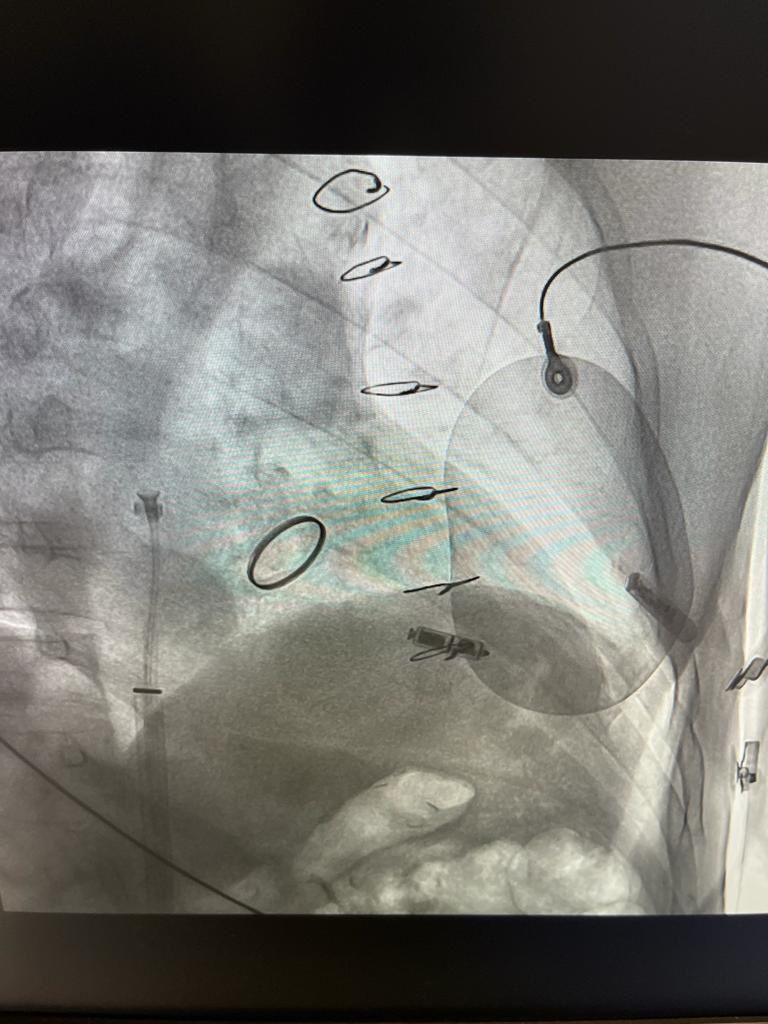

Effettua procedure di ablazione transcatetere e studi elettrofisiologici endocavitari per la diagnosi e il trattamento delle aritmie cardiache, esegue inoltre impianti di pacemaker, defibrillatori e dispositivi di resincronizzazione cardiaca per il trattamento dello scompenso cardiaco.